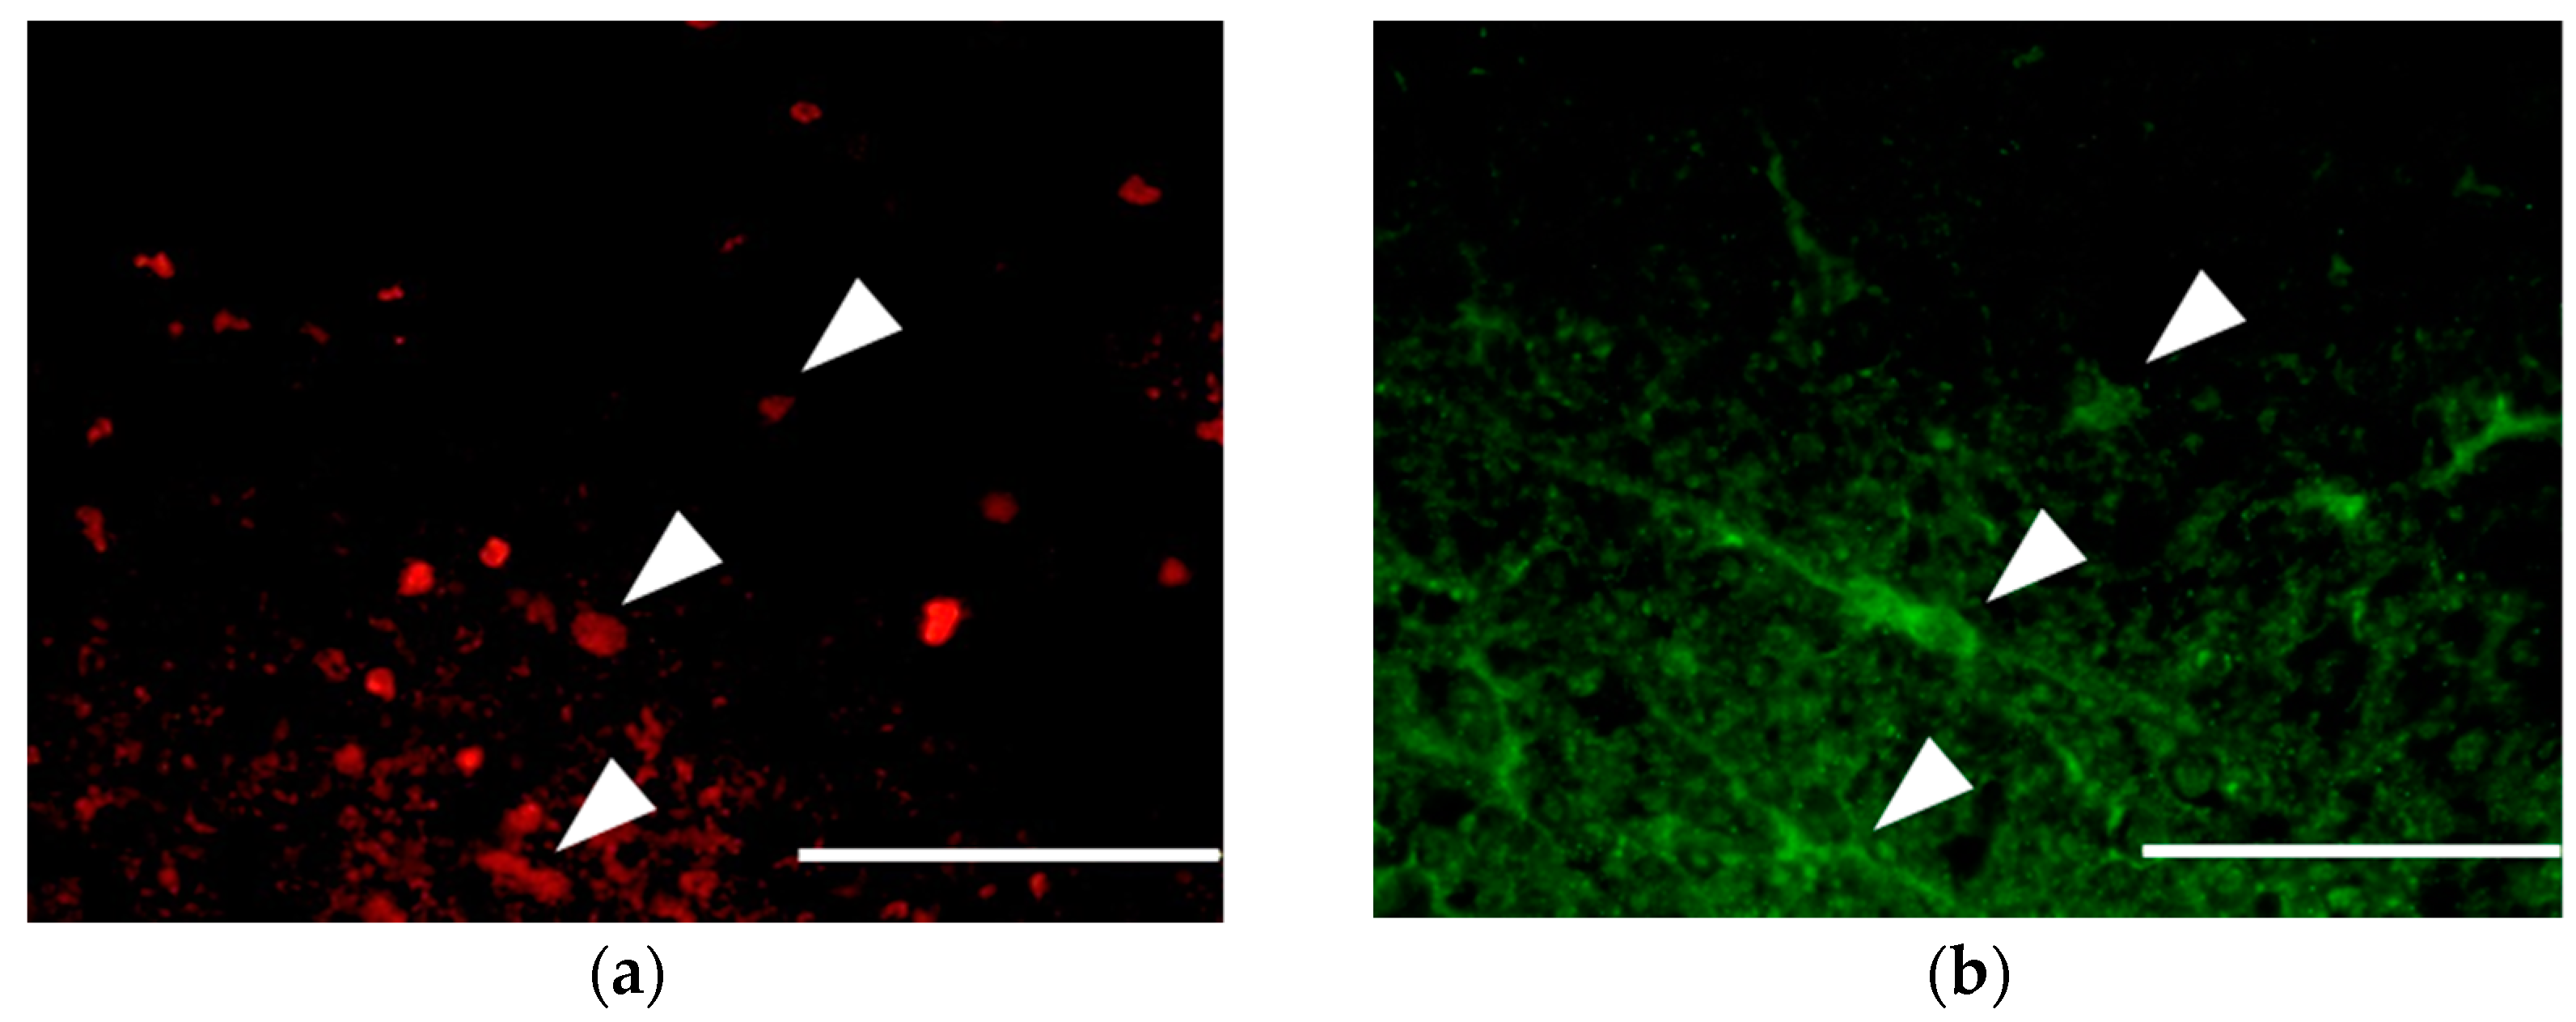

Immunohistochemistry revealed BrdU-positive cells at the periphery of the glia scar in the dorsal funiculus, indicating that neural cells replicated at that location between 12 to 72 h after SCI. Specifically noting the BrdU-positive OPCs that proliferated during the period after SCI, the number of BrdU- and NG2-positive OPCs peaked in both the amiloride and PBS groups at day 14. However, the number of new OPCs was significantly higher in the amiloride group than in the PBS group (amiloride group: 99.25 ± 22.69, PBS group: 60.80 ± 8.33, per section, p < 0.05) (Figure 3). Thereafter, we observed a gradual increase in the number of BrdU- and APC-positive oligodendrocytes that differentiated from OPCs proliferating after SCI. The amiloride group had a significantly greater number of BrdU- and APC-positive oligodendrocytes at day 56 than the PBS group (amiloride group: 42.40 ± 9.07, PBS group: 27.00 ± 9.91, per section, p < 0.05) (Figure 4), indicating that the decrease in OPC apoptosis caused by amiloride treatment led to an increase in the number of oligodendrocytes that differentiated from these OPCs.

(a–c) Double immunostaining of the dorsal funiculus from the amiloride group at day 14 for BrdU (red) and NG2 (green) with 4′,6-diamidino-2-phenylindole (DAPI) nuclear counterstaining (blue). The arrowheads indicate the BrdU- and NG2-positive cells (scale bars 50 μm); (d) In both the amiloride and PBS groups, an increase of BrdU- and NG2-positive cells was observed at day 14, followed by a decrease to day 56. Significantly more BrdU- and NG2-positive cells were observed in the amiloride group compared to the PBS group on day 14. The asterisk indicates significant difference between the amiloride and PBS groups with a Mann–Whitney U test (* p < 0.05, n = 5 per group, error bars are standard deviations).

Figure 4.

(a–c) Double immunostaining of the dorsal funiculus from the amiloride group at day 56 for BrdU (red) and adenomatous polyposis coli (APC) (green) with DAPI nuclear counterstaining (blue). The arrowheads indicate the BrdU- and APC-positive cells (scale bars 50 μm); (d) In both the amiloride and PBS groups, the number of BrdU- and APC-positive cells increased after SCI. Significantly more BrdU- and APC-positive cells were observed in the amiloride group than in the PBS group on day 56. The asterisk indicates significant difference between the amiloride and PBS groups with a Mann–Whitney U test (*p < 0.05, n = 5 per group, error bars are standard deviations).